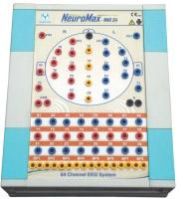

RS Enterprises is one of the noteworthy suppliers of a wide array of highly operational machines. We deal in EMG machine, ECG machine, Neuro Modulation Machine, Digital Biofeedback Machine, Therapy ECT Machine, Transcranial Magnetic Stimulation Machine, Sleep Study Machine, Pulmonary Function Test Machine, Digital Polygraph Machine, Digital Physiograph Machine, Digital Plethysmometer Machine, AD629 Diagnostic Audiometer, AD226 Diagnostic Audiometer, Channel ECG Machine, Electric OT Table and many more. As a respected name in the industry, we procure the entire range of products only from the reliable manufacturers or vendors after checking against numerous quality parameters such as functionality, maintenance, manufacturing defect, etc. We are capable of undertaking bulk as well as urgent orders as we maintain a streamlined inventory management system.